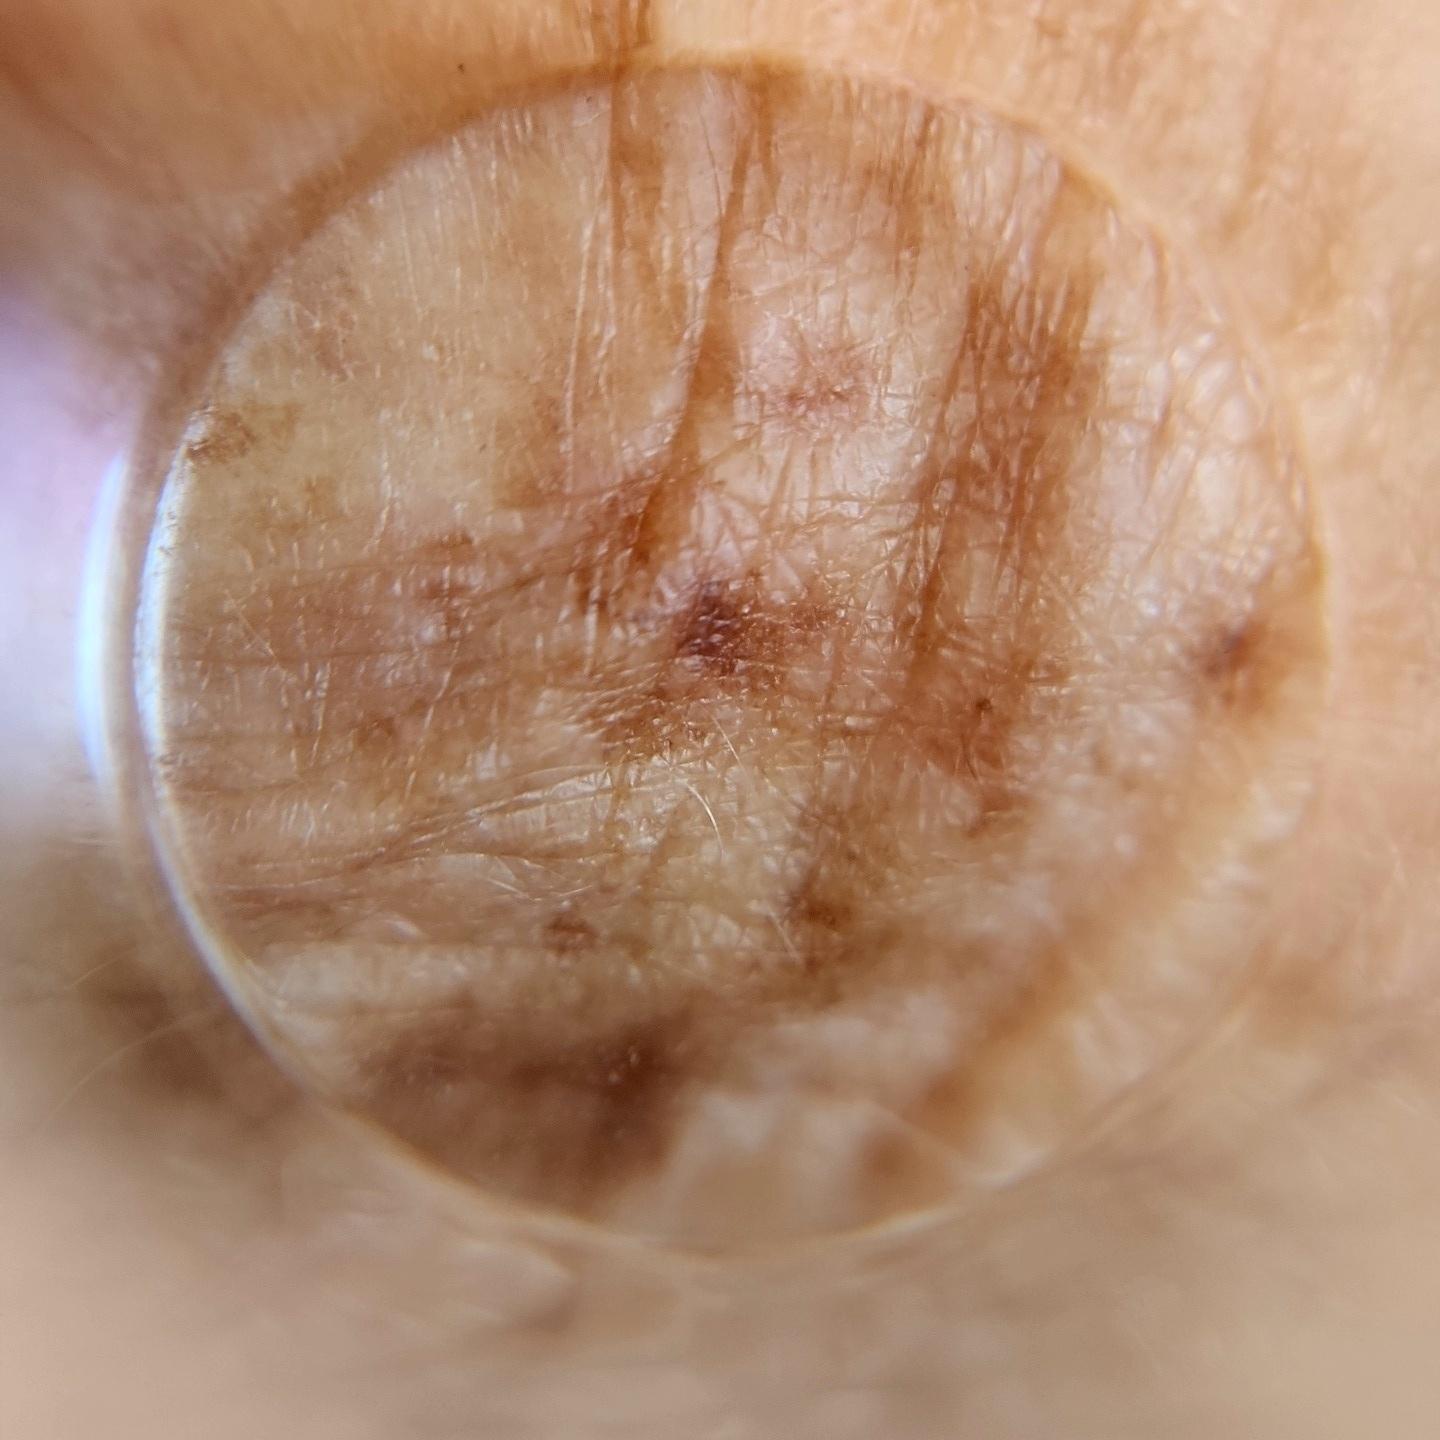

ISIC_4949599

Clinical

Field Value

diagnosis_1 Benign

image_type dermoscopic